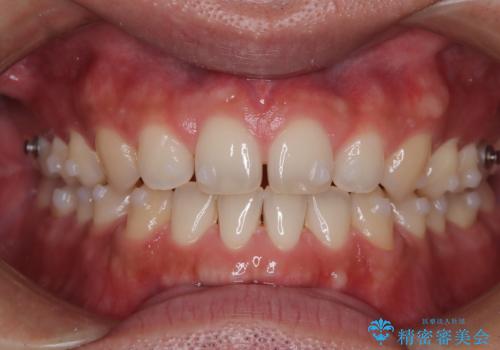

前歯の隙間が気になる マウスピース矯正

- 前歯がすきっ歯であることを気にされて来院された患者様です。上下顎のアーチを整える治療計画を立案し、マウスピースにて治療しました。とてもまじめに使用していただき、気になっていた隙間も順調に閉鎖しました。